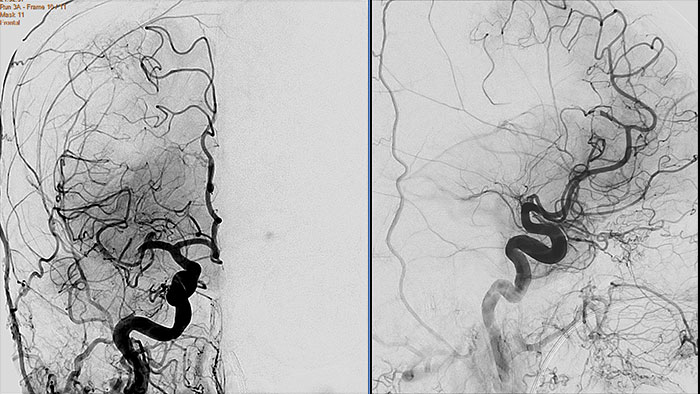

Contrast arterial structures with surrounding bone and soft tissue to assist in identification of vascular abnormalities

The XA Vascular Processing – DSA (in MMV) expands your workflow by allowing you to read and post-process iXR images virtually anywhere. Obtain images of arteries in various parts of the body using tools to perform standard and run subtractions, pixel shifting, and landmarking. This application also provides post-processing tools to edit and optimize the DSA XA data created in the interventional room.

Benefits

Comprehensive reviewing tool for multiple modalities, all in a single viewer

The Multi Modality Viewer (MMV) now supports viewing and post processing of angiography images and series. Review and perform analysis of angiographic imaging alongside other modalities for a comprehensive review of the patient case. Perform vascular processing of images (Digital Subtraction Angiography) – subtraction, pixel shifting and land marking. Include key images into the generic MMV report. Prior to the intervention, relevant diagnostic (MR and or CT) data can be bookmarked and automatically retrieved upon patient selection in the Allura, or the Azurion suites.